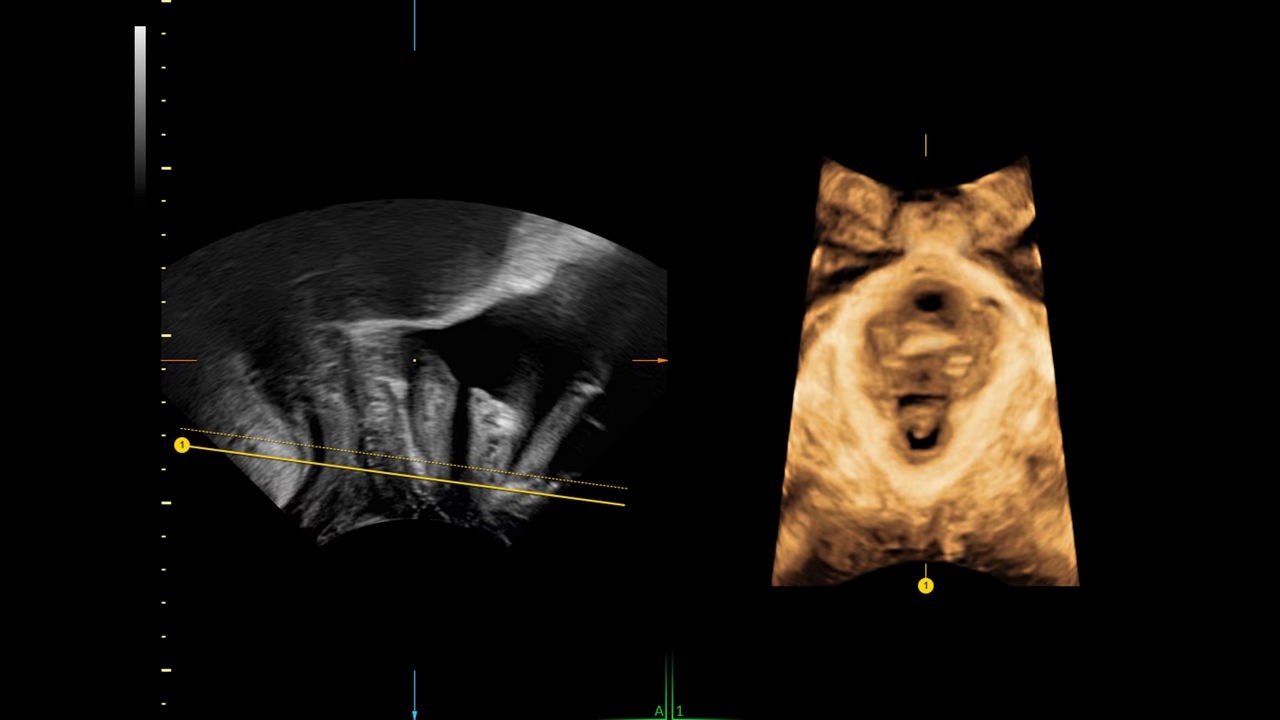

Obtain the coronal plane of the Uterus in ½ the time